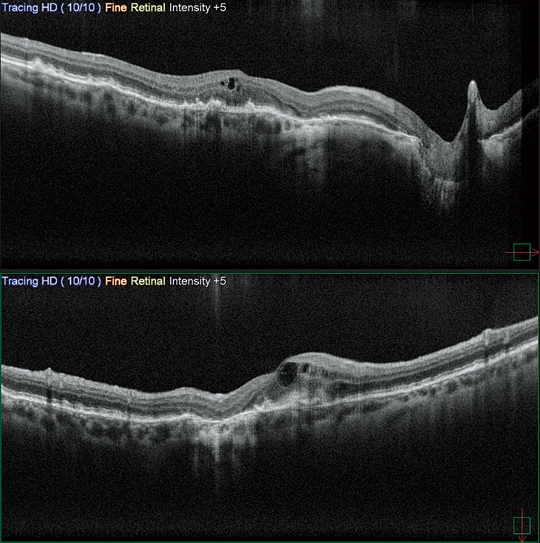

高清廣域OCT*

Mirante的掃描區域可達16.5 x 12毫米,單次拍攝就可實現包括黃斑和視盤的廣域診斷。超精細模式和高清自動追蹤功能可提供從玻璃體到脈絡膜的高質量圖像來觀察細微的病理改變。

* 適用于SLO/OCT型。